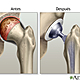

• Reemplazo articular en la Actualidad

Reemplazo articular en la Actualidad

El reemplazo articular es hoy en día un proyecto multidisciplinario donde colaboran cirujanos ortopédicos, bioingenieros, diseñadores de prótesis, estadísticos e informáticos.

El último período del desarrollo de los tratamientos de articulaciones artrósicas todavía es experimental y se orienta hacia la célula cartilaginosa y su capacidad para diferenciarse o regenerarse a partir de una célula precursora, y así tratar de restaurar la función de la articulación enferma.